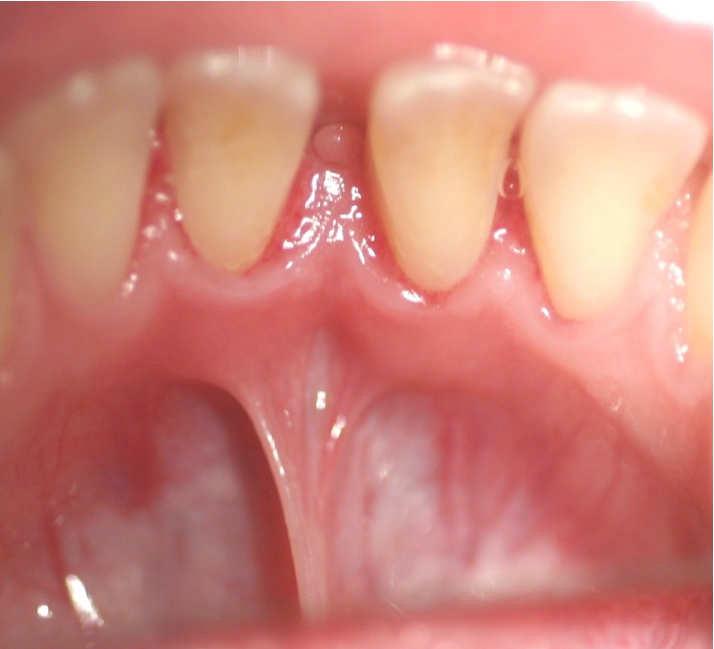

Diode Laser 810nm

Power: 2.5 Watt,

Pulsed 50 Hz ,Fibre 400 micron

Frenotomy-Tongue